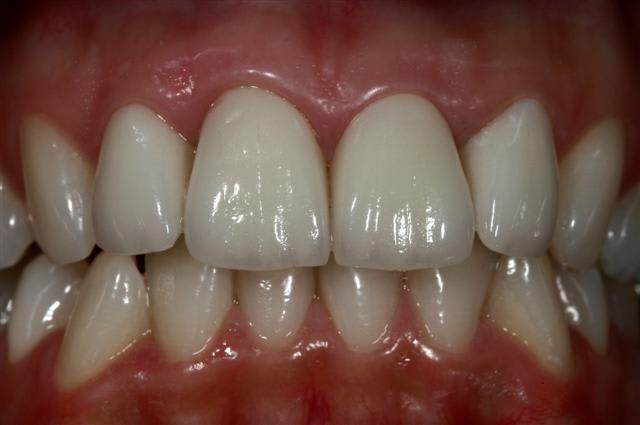

Controle à 1 semaine, patiente ravi et tout sourire... moi aussi :)

oui taille définitive, vivante, collée au RelyX Transp

Je fais un bonding le jour des preps. Je mets deux couches. Cela limite bcp le risque de sensibilité, et permet bien souvent de faire l'empreinte sans anésthésie. Mais pas toujours. Mais attention, bonding aprés avoir rebasé les provisoires, sinon aie aie aïe !!!. Pour faire tenir les provisoires, le mieux c'est:

Si on a fait un bonding : Dical

Si pas de bonding: Composite fluide sans mordançage et adhésif bien sur.

Le collage j'ai fait au relyx Transparent. C'est la première fois que je l'utilise pour un cas en empress...